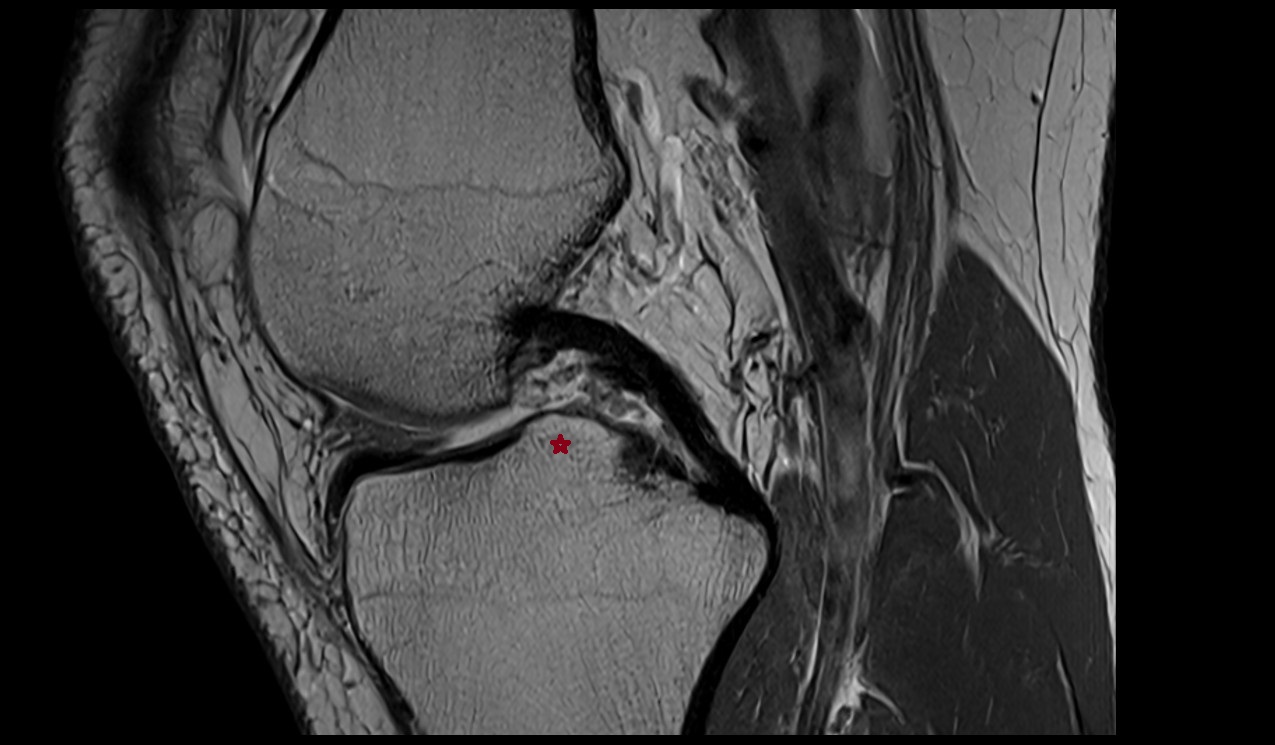

- Knee Joint